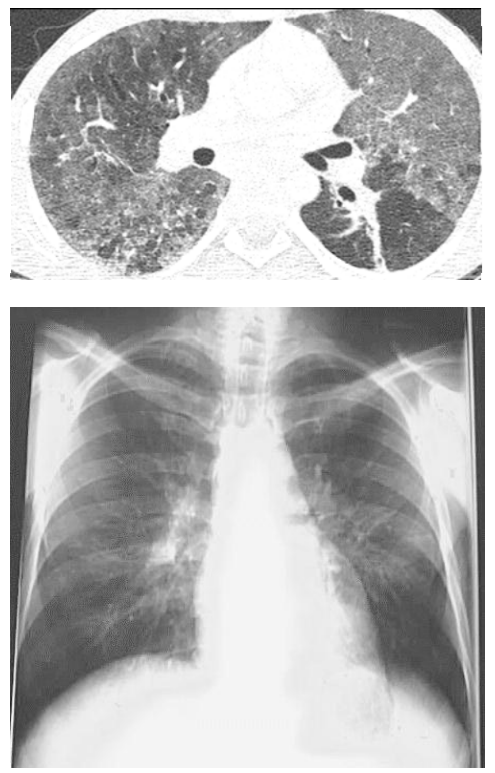

Um homem de 29 anos de idade, a princípio sem antecedentes, procurou o serviço de pneumologia com relato de dispneia progressiva, tosse seca, sensação de febre ao final da tarde e dor para deglutir. Relatou ter feito sexo desprotegido mais de uma vez no passado. Ao exame físico: lúcido e orientado em tempo e espaço; afebril; acianótico; anictérico; hidratado; taquipneico; FR de 30 irpm; FC de 60 bpm; PA de 112 × 80 mmHg; sat. de O₂ de 92% em ar ambiente; e oroscopia com placas esbranquiçadas e base eritematosa em cavidade oral. Exames complementares: Hb 13 g/dL; 15.900 leucócitos, com 7% de linfócitos e 70% de neutrófilos, com desvio à esquerda; 264.000 plaquetas; escarro com BAAR negativo; e DHL 900 U/L. Gasometria: pH 7,44; PO2 62 mmHg; PCO2 22 mmHg; e BIC 26.

Com base nesse caso hipotético, assinale a alternativa que apresenta o manejo no momento.